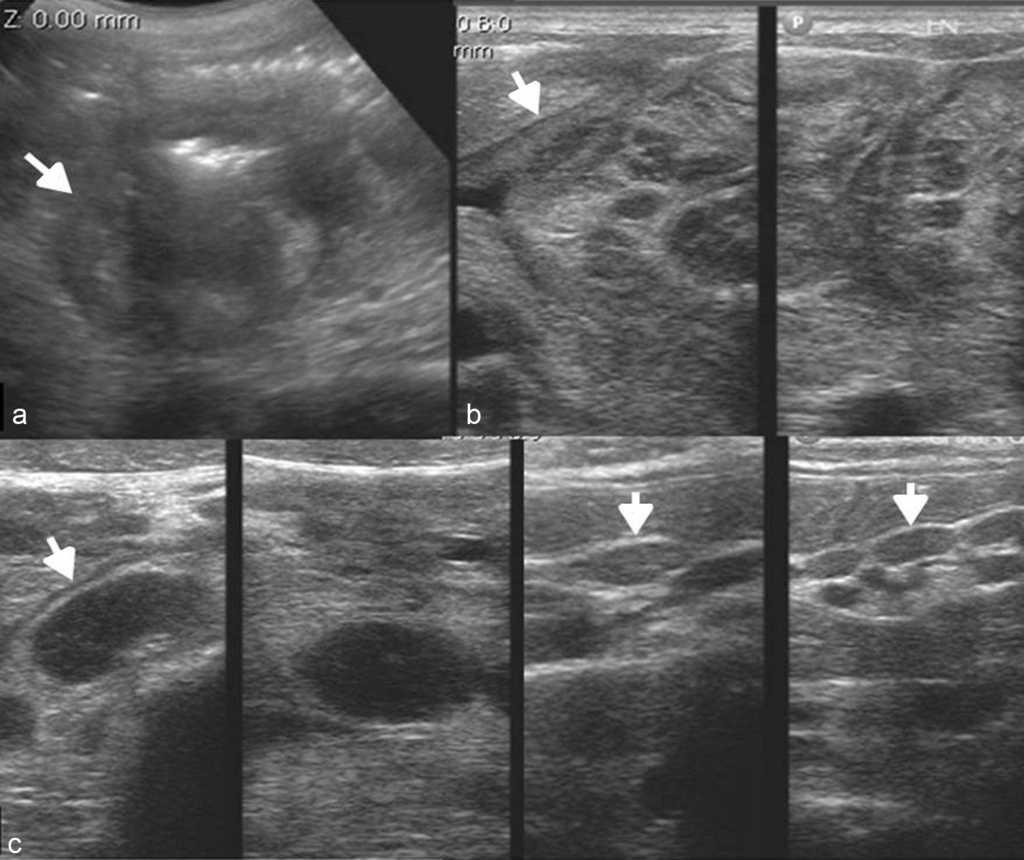

La ecograf??a es el m??todo ideal para la exploraci??n del sistema musculoesquel??tico, en tanto brinda la posibilidad de evaluarlo en reposo o en movimiento, observando los cambios en tiempo real. Adem??s, permite la comparaci??n del sitio exacto del dolor con su lado contralateral, adquiriendo im??genes en panor??mica19.

Los actuales transductores de alta frecuencia (12-18 MHz) tienen excelente resoluci??n para analizar las estructuras superficiales (m??sculos, tendones, ligamentos y bursas) y sus patolog??as20 (figs. 14 y 15). La ecograf??a en escala de grises permite una gran imagen anat??mica de la lesi??n, mientras que el Doppler color identifica la vascularizaci??n del tejido y las im??genes panor??micas otorgan una visualizaci??n extensa del campo de visi??n, que muestra la lesi??n y su relaci??n con las estructuras vecinas (fig. 16).

A pesar de estas grandes ventajas, muchos profesionales elijen otras modalidades diagn??sticas por m??ltiples razones21. Al respecto, vale subrayar que es necesario un profundo conocimiento de la anatom??a de la zona a explorar y su cl??nica para obtener los mejores resultados.